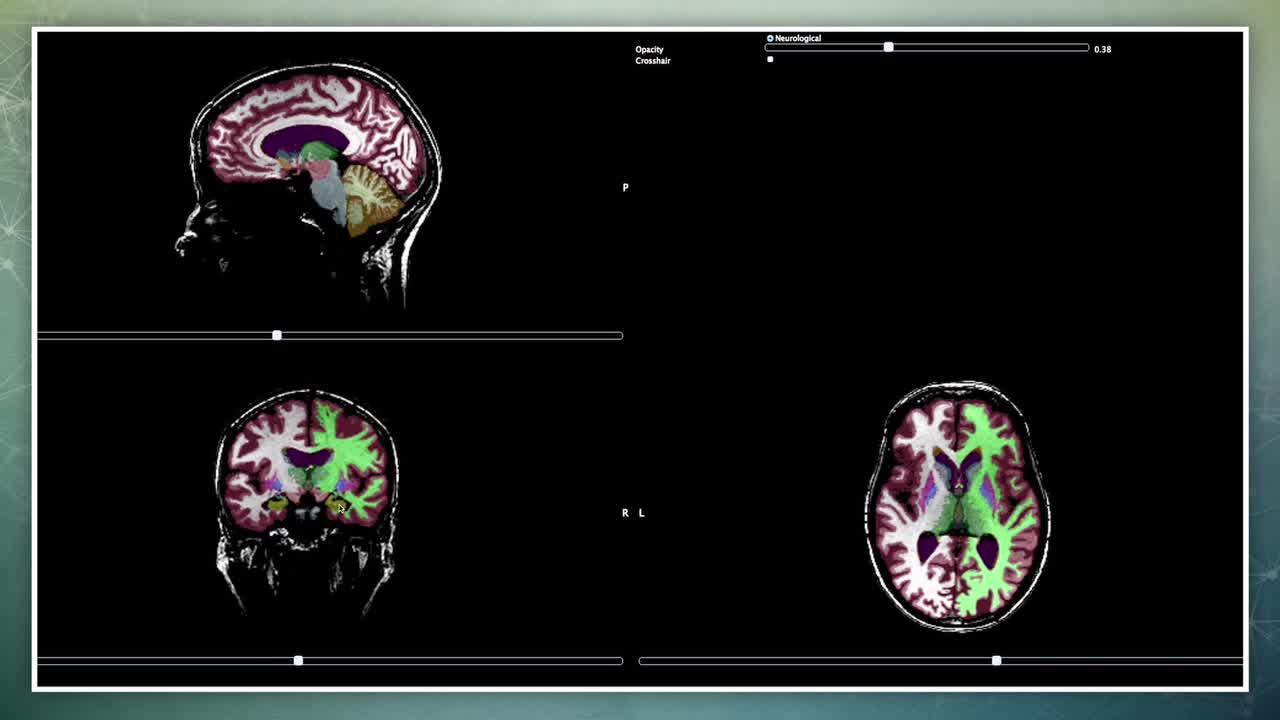

神经影像软件在实践和研究中的应用

先进的神经诊断软件有助于医生制定更好的治疗计划